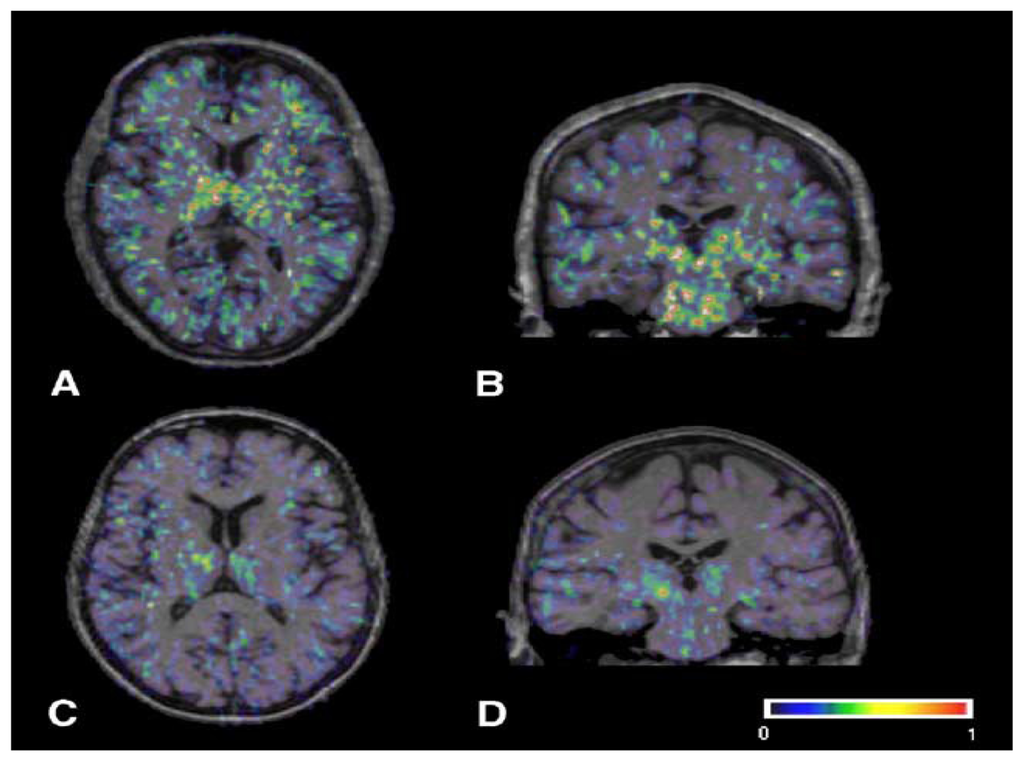

- Ouchi, Y; Yoshikawa, E; Sekine, Y; Futatsubashi, M; Kanno, T; Ogusu, T; Torizuka, T. Microglial activation and dopamine terminal loss in early Parkinson’s disease. Ann. Neurol 2005, 57, 168–175. [Google Scholar]

- Gerhard, A; Pavese, N; Hotton, G; Turkheimer, F; Es, M; Hammers, A; Eggert, K; Oertel, W; Banati, RB; Brooks, DJ. In vivo imaging of microglial activation with [11C](R)-PK11195 PET in idiopathic Parkinson’s disease. Neurobiol. Dis 2006, 21, 404–412. [Google Scholar]